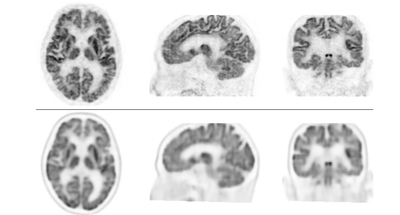

検証では、認知機能障害、てんかん等の18名の患者において、脳FDG-PET装置を用いて撮像した画像と、本PET装置で撮像した画像を比較しました。次に、認知機能障害患者17名において、従来のPET/CT装置を用いた画像と本PET装置で撮像した画像を比較しました。その結果、全例において本PET装置による画像の分解能が優れており、従来型よりも分解能が高く、細かいところまで描出できることが示されました。

臨床研究では、主に認知症患者に対し、ブドウ糖代謝とアミロイド※4沈着の有無をみる検査を行い、本PET装置と従来のPET/CT装置で撮像した画像を比較検討しました。その結果、全例において本PET装置で撮像した画像の分解能が優れていることが明らかとなり、症例によっては診断が変わることさえありました。これにより、臨床使用においても、本PET装置が正確な診断を可能にし、認知症の早期治療に貢献するものであることが示されました。